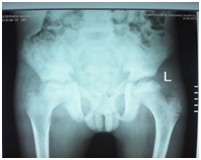

A 12-year-old boy was diagnosed with Sickle Cell Disease (SCD) with genotype SS about one year prior to. He presented with 2 months history of inability to walk and pain in both legs to Komfo Anokye Teaching Hospital in Kumasi, Ghana. The complaints were associated with marked weight loss and generalized body pain. He had been admitted about 2 weeks prior to the onset of current symptoms on account of abdominal pain and anaemia where he was haemo-transfused, given medications and subsequently discharged. There were no other significant findings in the past medical history, immunization history, nutritional and developmental histories. On examination he was found to be wasted (Weight for Height z-score <-3SD), pale, afebrile and anicteric. He had palpable axillary and inguinal lymph nodes (each measuring about 1cm to 1.5cm, mobile, non-tender and not matted). Vital signs were normal on admission. Other significant examination findings were obvious swelling of the right leg which was warm to touch, erythematous and tender on palpation. He had a gibbus deformity of the lower thoracic spine with no remarkable neurological findings in the lower limbs. A diagnosis of SCD with vaso-occlusive crises and cellulitis of the right leg was made with differential diagnosis of osteomyelitis, Deep Vein Thrombosis and Potts disease. Initial investigations revealed WBC of 13.51 X 109/dl with Neutrophils 8.83 (65.3%) Lymphocytes 4.27 (31.6%) and Monocytes 0.25(1.9%), Hemoglobin 7.1g/dl, MCV-70.7, MCH-22.4, Platelets: 538, ESR-117, INR-1.05, Prothrombin Time-14.3secs and blood sugar-6.5mmol/L. Malaria parasites were not seen on the blood smear and patient was negative for Retro-Viral Screen for HIV. Other investigations included Doppler Ultrasound, Chest X-ray, Pelvic x-ray, Thoraco-lumbo-sacral spine X-ray (Figure 1-10). Blood culture and sensitivity could not be done at the time of admission as microbiology service in the hospital had a brief logistic challenge. Radiological findings revealed the following: Reduction in the vertebral body heights of T7-T10 with associated reduction in the intervertebral disc spaces and crowding of the posterior ribs. A paravertebral soft tissue mass extending from T4 vertebral level to T11. Coarse trabeculation and sclerosis of the ribs noted. Expansion of the anterior end of the left 8th rib with ill-defined lytic areas. Buckling of the cortex of the lateral aspect of the left 9th rib, suggestive of a fracture. The imaged portion of the proximal humerus shows periarticular osteopenia. Also noted was relatively small left humeral head with left glenohumeral joint space. There are patchy homogenous opacities in both lung fields predominantly in the lower zones. There was associated silhouetting of the hemi diaphragms bilaterally and the cardiac shadow. There was generalized sclerosis of the imaged pelvic bones with coarsening of the trabeculae. The right femoral head was deformed and expanded with sclerosis and lytic areas within. There was associated narrowing of the right hip joint space. The left femoral head also showed patchy lucencies. No deformity of the left femoral head seen. The left hip joint space appeared normal. Also noted was fusion of the sacroiliac joints bilaterally. There was diffuse sclerosis of the imaged vertebrae with coarse trabeculae. The vertebral endplates of L1/L2 and L3/L4 showed sharp depression at the margins with a flat base centrally giving it the H shaped appearance. Also noted were ill-defined lytic areas in the L3 to L5 vertebrae with associated end plate irregularities and reduced intervertebral disc spaces at L3/L4 and L4/L5. No paravertebral soft tissue mass seen. No fracture or listhesis seen. Changes of the thoracic spine were described under the chest x-ray.

These radiological diagnostic features were suggestive of sickle cell disease with Thoracolumbar spondylodiscitis, likely pyogenic; Bilateral Avascular Necrosis of the femoral head (early on the left); Septic arthritis of the right hip and left shoulder joint; Osteomyelitis of the left 8th and 9th ribs. Doppler Ultrasound of the lower limb revealed the following: The right common femoral and superficial femoral veins were of normal lumen with good wall to wall compressibility, good colour doppler and spectral wave form properties. The right popliteal and posterior tibial veins however showed extensive echogenic intraluminal-filling defect with resultant loss of wall-to-wall compressibility (percentage stenosis 76%). The accompanying arteries were of normal size and caliber and showed good colour doppler and spectral properties. There was thickening of the subcutaneous tissue with dilated fluid channels seen in the right foot. Inguinal as well as popliteal lymph nodes with retention of their fatty hilum noted averaging 0.9*0.5cm. Also noted was a 1.4*0.9*1.5cm (volume about 1.0ml) anechoic collection with low-level internal echoes at the medial aspect of the proximal thigh muscles; suggestive of inflammatory changes. Based on the Doppler findings a clinical diagnosis of Right Popliteal and Posterior Tibial Vein Thrombosis with Pyomyositis in a Sickle Cell Disease patient was considered and patient was subsequently administered subcutaneous Enoxaparin 40mg daily as well as Warfarin 3mg nocte, IV Clindamycin 150mg qid, IV Ciprofloxacin. After 2 days of Warfarin and Enoxaparin, INR and PT were repeated and results were 1.1 and 15.1s respectively. The child was followed up closely for four weeks and subsequently discharge. A repeat Doppler finding revealed a completely resolved thrombus with no evidence of DVT.